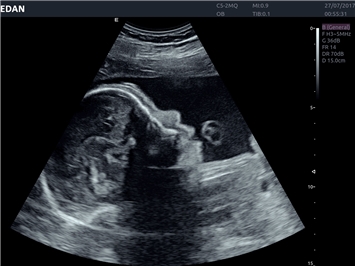

EDAN Acclarix LX4 представляет собой инновационную ультразвуковую систему, построенную на усовершенствованной платформе Acclarix. Сочетание высокого качества визуализации с интеллектуальным рабочим процессом делает эту систему оптимальным выбором для клиник, ценящих эффективность и экономичность.

• 3D/4D-визуализация с автоматическим редактированием объема (eFace)

• Автоматизированные измерения в акушерстве

• Акушерства и гинекологии

3D/4D:

Да